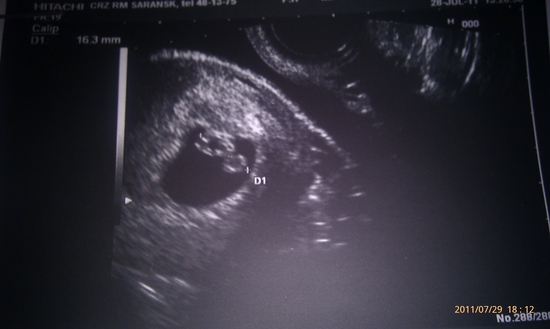

Узи делали минут 20. Сказали, что дочка будет. По параметрам все вроде как хорошо (ТТТ). Я на радостях, даже забыла что обижалась на него, вышла и звоню. А он оказывается меня около моей машины на парковке ждет. короче вот так вот. Мы такие счастливые

Ведь нам уже 6 неделек и 4 дня.